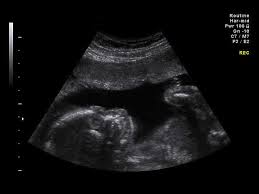

Ultrasound (Anatomy Scan)

When: 18–22 weeks, 6–7 (Weeks 23–28) — Second Trimester / Early Third Trimester

Why: Ultrasound to examine fetal anatomy (brain, heart, spine, etc.) for structural abnormalities, monitors, detects multiple pregnancies, and evaluates placental position.

Method: Detailed ultrasound scan

How it’s done: A detailed ultrasound where gel is applied to the mother’s belly, and a transducer (ultrasound wand) is used to visualize the baby’s organs, limbs, and overall growth.